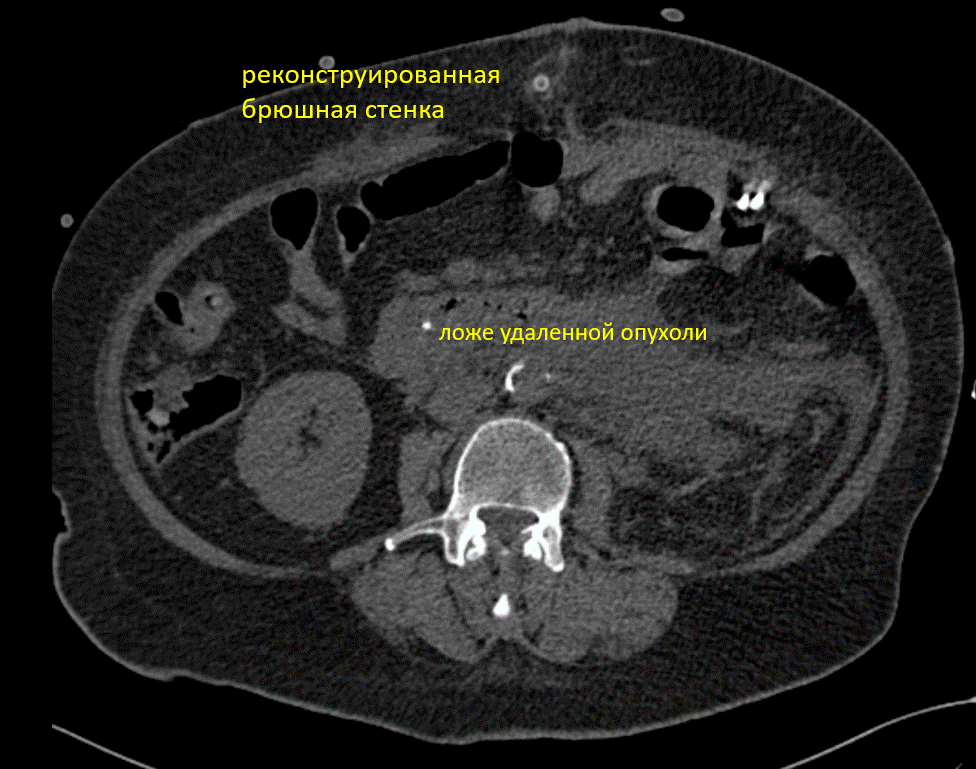

Очень часто пациентам с онкологическим заболеванием отказывают в операции в связи с многочисленными рисками. Более того, часто этим пациентам отказывают даже в лечении, т.к. признают этих пациентов неизлечимыми. Хочу поделиться видео-отзывом одной из моих пациенток, которая обратилась в клинику «Медицина 24/7» после самых неблагоприятных прогнозов, поставленных другими врачами. Действительно ситуация была не простая - опухоль в брюшной полости весом свыше 5 кг. После проведения химиотерапии, размер опухоли уменьшился и стабилизировался, это позволило провести оперативное вмешательство по удалению образования. Впереди дальнейшее лечение.